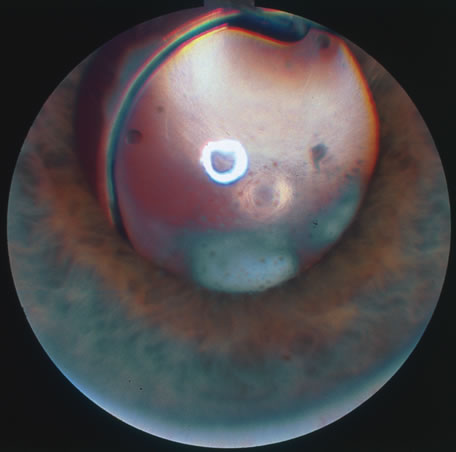

In primary ocular HSV infections, a severe follicular conjunctivitis with regional adenopathy is present. Vesicles may appear on the eyelid skin or lid margin, producing blepharitis (Fig. 3). Corneal involvement initially takes the form of a superficial punctate keratitis, which may progress to dendritic or geographic ulceration. Stromal infiltrates and uveitis are less common and relatively mild in primary disease. In uncomplicated cases, lesions usually heal completely in 2 to 3 weeks without scarring. Most cases of ocular HSV are recurrences. Recrudescent ocular herpes may take the form of dendritic or geographic ulcers, recurrent erosions, interstitial or disciform stromal keratitis, and anterior uveitis.3 HSV may also be an agent of retinitis and acute retinal necrosis (Fig. 4).

The acute retinal necrosis (ARN) syndrome is most often caused by the herpes zoster virus, although occasionally it may be a result of herpes simplex infection.12 It is typically described in healthy patients although association with immunosuppressed patients has also been described. Granular, nonhemorrhagic areas of retinal necrosis may be observed in the fundus, often rapidly coalescing with resulting blindness often caused by retinal detachment. There is often an associated vasculitis and vitritis. In immunocompromised patients VZV or HSV retinitis may also take the pattern of progressive outer retinal necrosis (PORN) (Fig. 6). PORN differs from ARN in that the former is multifocal, localized to the outer retina, and is less often associated with vasculitis and vitritis.